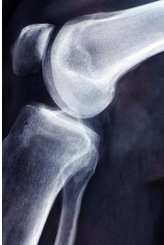

무릎 연골 손상 증상 원인 치료방법 알아봐요

무릎 연골 손상 증상 원인 치료방법 알아봐요 무릎 연골 손상은 예방이 가장 중요합니다. 적절한 운동 기술과 보호 장비의 사용은 부상을 예방하는 데 큰 도움이 됩니다. 또한 근력 강화 운동과 스트레칭을 통해 무릎 관절을 강화하고 유연성을 유지하는 것도 중요합니다. 만약 부상이 발생한다면, 즉시 휴식을 취하고 전문의의 진단과 치료를 받아야 합니다.

무릎 연골 손상 증상

- 무릎 붓기, 통증: 연골이 손상되면 관절에 염증이 생기고 부종이 발생합니다. 부종은 무릎 관절을 둘러싼 조직에 수분이 많이 축적되어 무릎 관절이 붓고 뻣뻣해지기 때문에 발생합니다. 부종은 또한 통증을 동반할 수 있으며 무릎 관절의 움직임을 제한하거나 관절의 뻣뻣함을 유발하는 것으로 알려져 있습니다.

- 계단을 오르고 내릴 때 찌릿한 느낌: 연골이 닳거나 찢어지면 뼈와 뼈가 마찰하거나 연골 조각이나 결정체가 관절 내부에서 움직일 수 있습니다. 이때 계단을 오르거나 내리는 등의 움직임으로 인해 무릎에서 찌릿하거나 걸리는 듯한 느낌이 발생할 수 있습니다. 이러한 느낌은 통증과 관련이 있을 수 있으며 무릎의 움직임을 방해하거나 불안정하게 만들 수 있습니다.

- 힘 풀림: 연골 손상으로 인해 발생할 수 있는 근력 약화입니다. 근력 약화는 관절의 통증, 부기 또는 뻣뻣함으로 인해 발생할 수 있는 영향을 받는 부위 주변 근육의 위축과 약화입니다. 근력 약화는 통증이 동반될 수 있으며 무릎 움직임이 억제되거나 불안정해질 수 있습니다.

- 무릎을 구부리기 힘듬: 연골 손상으로 인해 발생할 수 있는 움직임 제한입니다. 움직임 제한은 관절의 통증, 부기 또는 뻣뻣함으로 인해 무릎을 움직이거나 걷기, 달리기, 앉기, 서기, 계단 오르내리기와 같은 일상 활동 및 운동을 수행하기가 어렵거나 불가능할 때입니다. 통증이 동반될 수 있으며, 움직이지 않으면 무릎 관절이 불안정해질 수 있습니다.